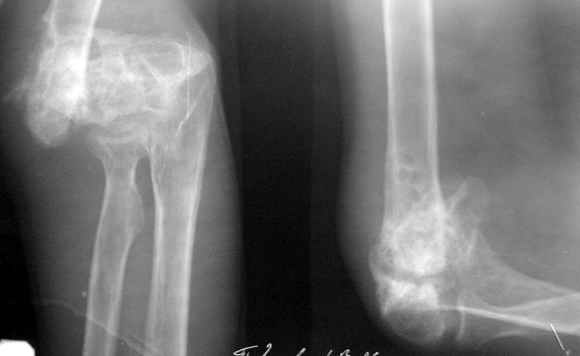

The recent x rays show established Non union with poor quality bone in the distal fragement. The joint is also appearing degenerate. In view of the multiple failed reconstructive surgeries, an Elbow replacement would seem reasonable.

However it would have to be a fully constrained one as there would be missing bone stock.

Obviously there is no elbow joint...the options are few: (from the worst to the "best"...if any)

1. Arthrodesis - last choice if at all

2. If no pain leave it as it is

3. Total elbow replacement (semi constrained - as no ligaments to stabilize the joint) - Coonrad-Morrey, Discovery - Biomet - considering his age there is limited indication for that procedure.